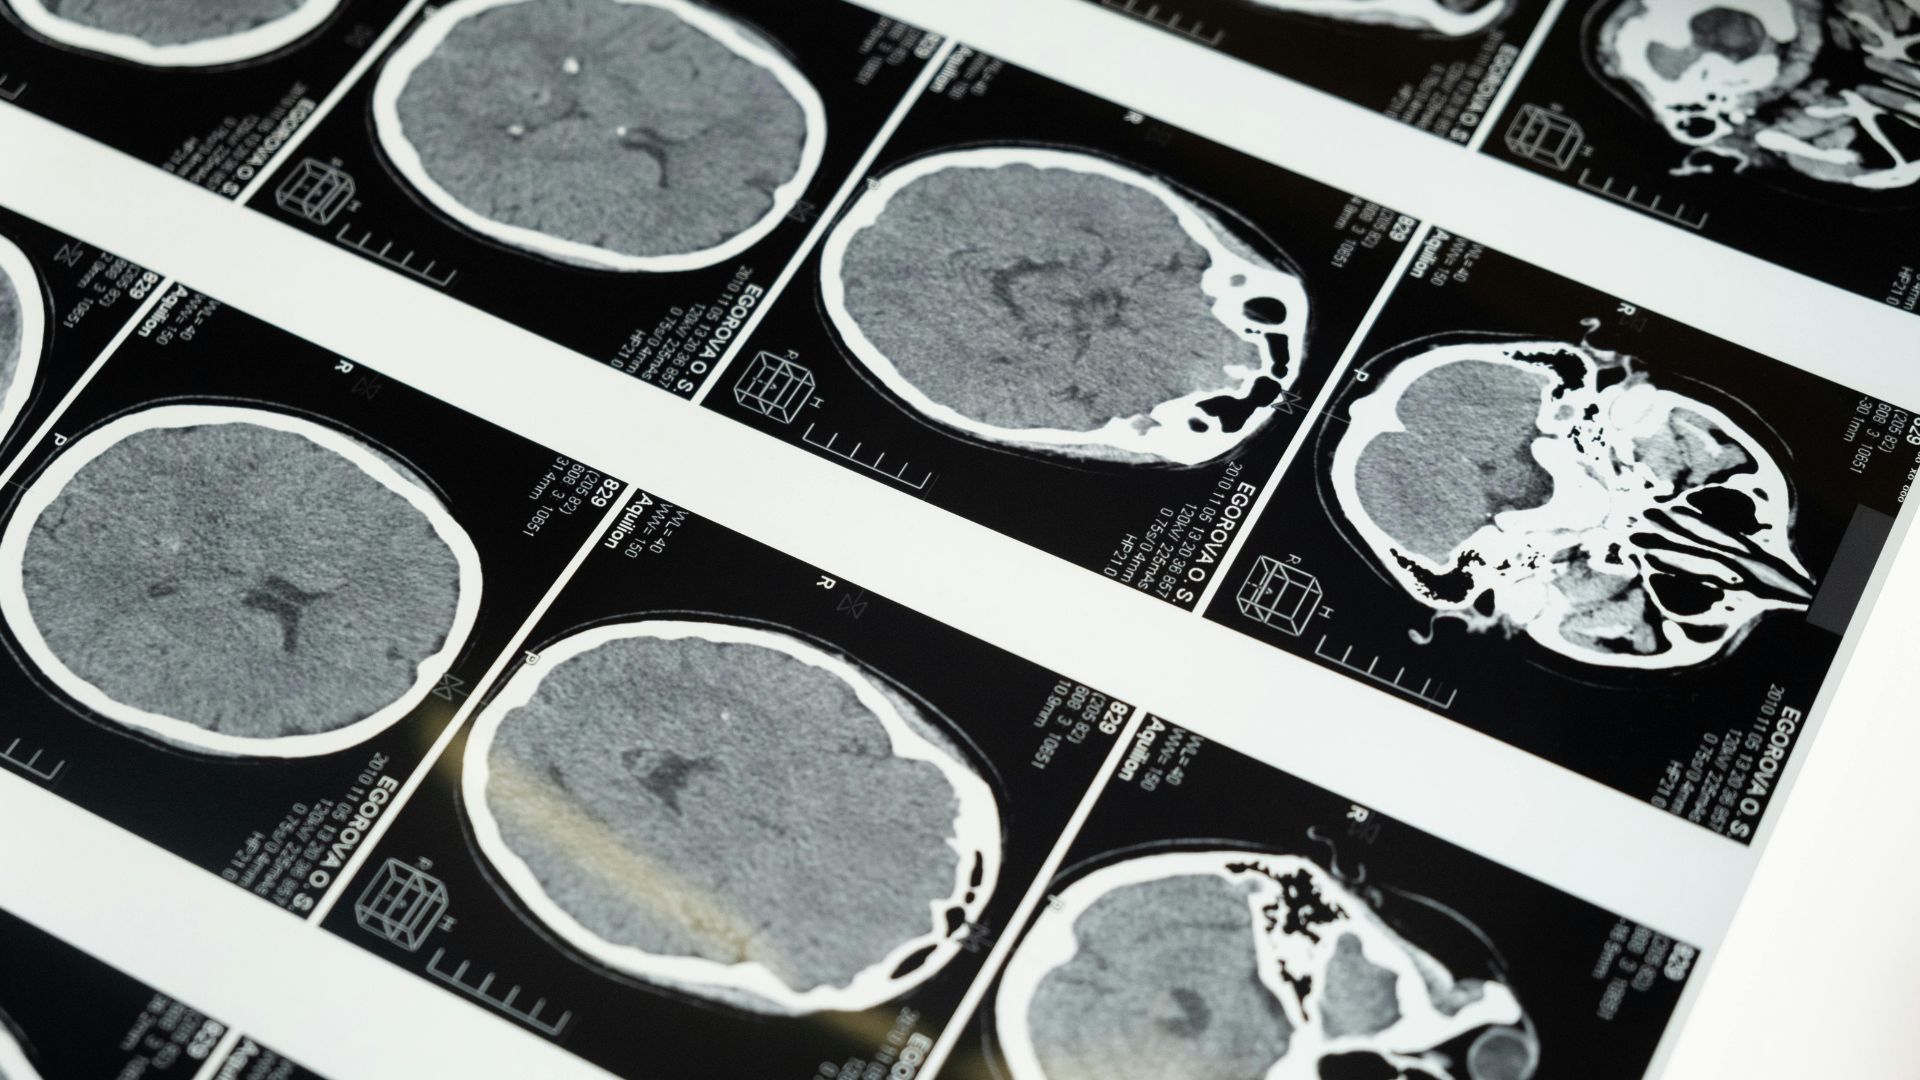

Recent research led by neurobiologist Prof. Dr. Hilmar Bading at Heidelberg University sheds new light on how Alzheimer’s disease advances at the cellular level. In collaboration with scientists from Shandong University, the team explored a specific mechanism that appears to accelerate the degeneration of brain cells. Using an experimental mouse model, they identified a critical interaction between proteins that may explain part of the cognitive decline seen in patients.